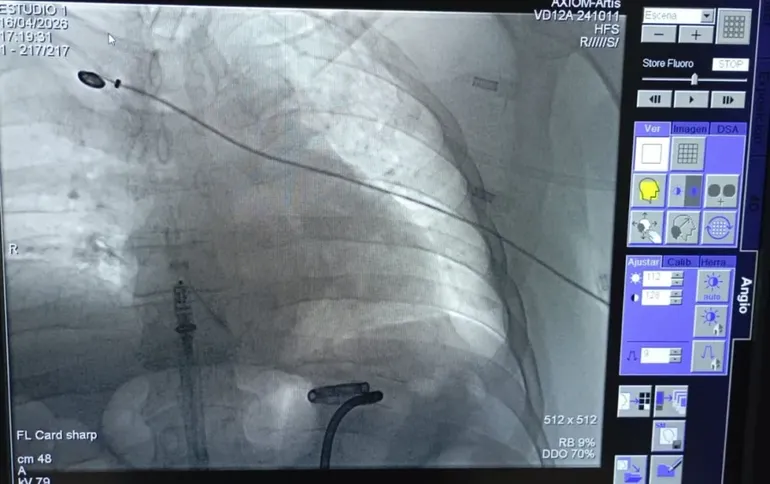

Una moderna intervención quirúrgica tuvo lugar en una clínica de Viedma marcó un valor sin precedentes ante el diminuto dispositivo colocado en el paciente. Se trata de un procedimiento realizado por el equipo del Servicio de Electrofisiología de la Unidad de Cardiología de la Clínica Viedma.

El equipo médico realizó la cirugía que se extendió por 40 minutos para la colocación del marcapasos más pequeño del mercado. Se llama Micra AV2, un dispositivo de la empresa Medtronic con un tamaño 10 veces más pequeño que uno convencional, con una batería que dura un 40% más y permite que el paciente pueda tener una vida plena.

La intervención estuvo encabezada por Martín Calvelo, jefe de Cardiología de la Clínica Viedma y bajo la supervisión de Ariel Estévez, un médico especializado en la implementación de estas cirugías.

El dispositivo fue colocado en un paciente de 56 años, quien presentaba un cuadro de infecciones de catéteres a repetición, es decir, las reiteradas infecciones impedían la implantación de un marcapasos convencional por la vía tradicional de la parte superior del cuerpo.

El médico que encabezó la cirugía, Martín Calvelo explicó: “Para su colocación, es necesaria una intervención quirúrgica que consiste en implantar un generador de impulsos eléctricos (pila o batería) y un cable-electrodo endovenoso. Un extremo del electrodo se coloca en la cavidad interna del corazón y el otro extremo se conecta al generador”.